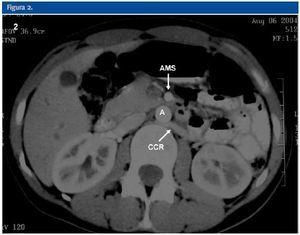

La ecografía Doppler, al igual que la TC realizada, demostró la compresión de la vena renal izquierda entre la arteria mesentérica superior (AMS) y la aorta abdominal (A). En la ecografía Doppler se demostraba un efecto de pinza sobre la vena renal principal izquierda (VRI) que se traducía en una asimetría de flujo venoso entre ambos riñones, siendo de amplitud y pulsatibilidad disminuída en el lado izquierdo. Se observaba también circulación colateral retroaórtica (CCR) con inversión de flujo en la vena ovárica izquierda. En la TC se evidenciaba circulación colateral retroaórtica (vena renal retroaórtica accesoria).

Figura 1.